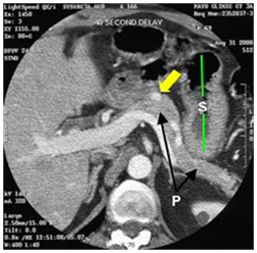

Although there is a potential "blind-spot" at the splenic hilum, a high sensitivity has been obtained. A recent single-centre prospective study showed a sensitivity of 93% and a specificity of 95% in localization of intra-pancreatic lesions. EUS could detect all tumors visualized by every other conventional technique, thus questioning the need for the rest imaging modalities (Figure 6–8).44–48

Figure 7a CT scan showing an insulinoma (white dot pointed to by yellow arrow) in the body of the pancreas (P with arrows pointing to the body and tail of the pancreas). The stomach (S with green lines up and down) has air (black) and fluid (darker gray) with it (stomach wall at end of lower green line). 42

Figure 7b CT scan showing insulinoma (white dot pointed to by yellow arrow) in junction of head and uncinate portions of pancreas. Just to the right of the insulinoma is the portal vein (white with "tail"–vein from the spleen joining it) carrying blood from intestine and pancreas to liver. 42